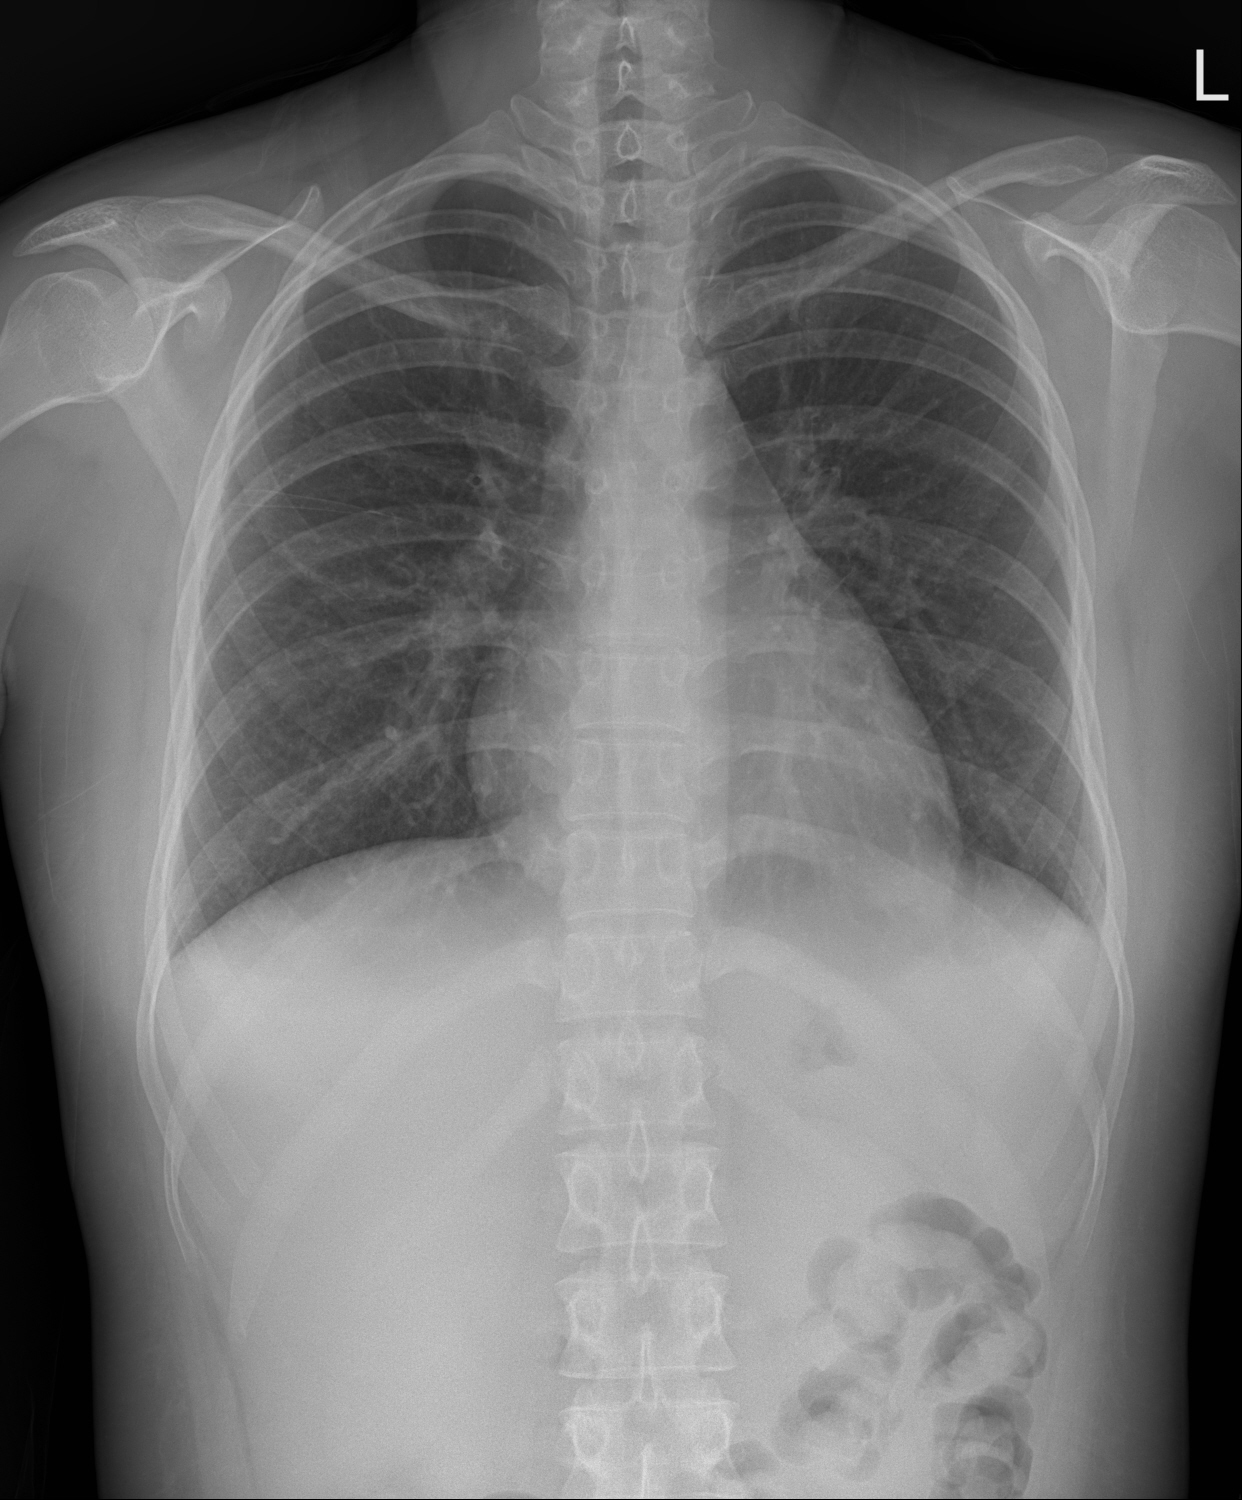

X-ray는 에너지가 높은 전자기파로, 인체를 통과하면서 조직 밀도에 따라 흡수 정도가 다릅니다. 뼈와 같은 밀도가 높은 조직은 X-ray를 많이 흡수하여 하얗게 보이며, 공기처럼 밀도가 낮은 부위는 X-ray가 통과하여 검게 나타납니다.

예를 들어, 흉부 X-ray에서 폐는 공기로 채워져 있어 어둡게 보이며, 갈비뼈는 하얗게 나타납니다. 이러한 차이를 통해 의사는 폐렴, 골절, 종양 등 다양한 질환의 유무를 확인할 수 있습니다.